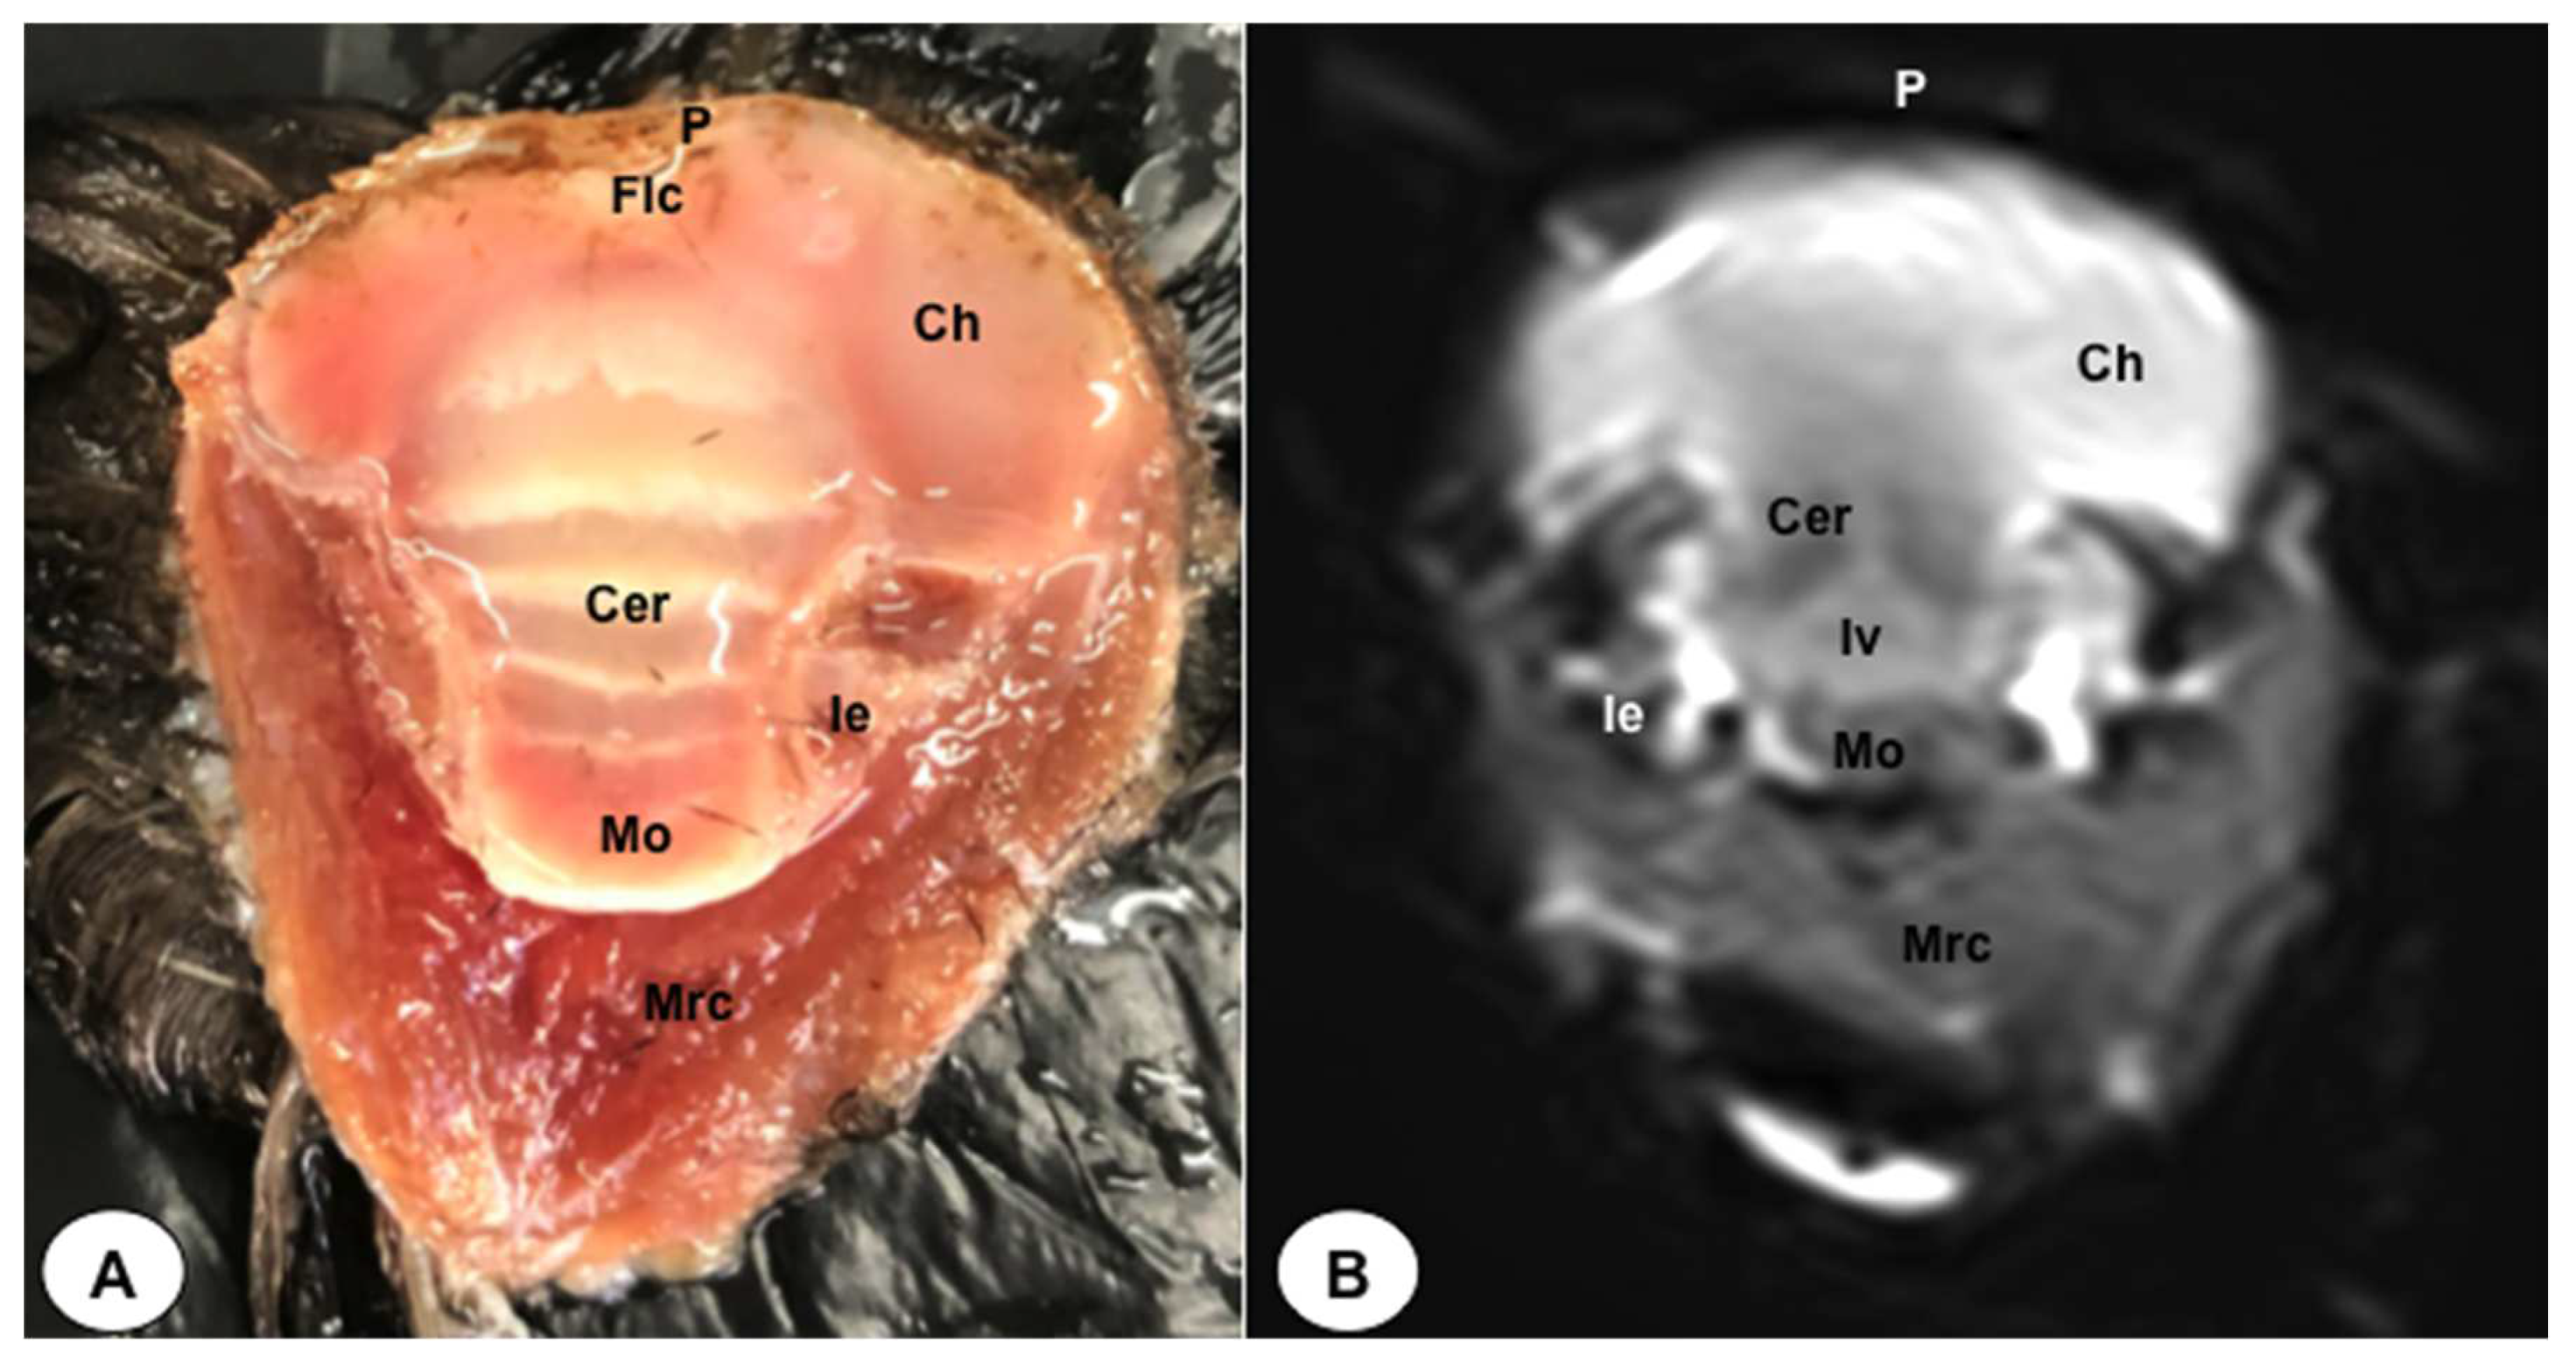

Figure 6. Dorsal cross-section (A) and T2W MR (B) images of the atlantic puffin head at the level of the medulla oblongata corresponding to line V inFigure 1. P: Os parietale; Flc: fissura longitudinalis cerebri; Ch: cerebral hemisphere; Cer: cerebellum (body); Mo: Medulla oblongata; Ie: inner ear. Mrc: Musculus rectus capitus (Musculus rectus dorsalis+ Musculus rectus ventralis+ Musculus rectus lateralis).